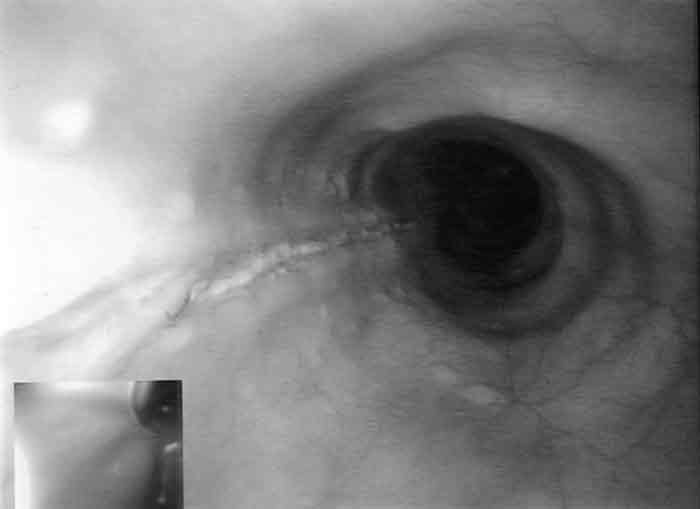

The patient was admitted and managed with nil by mouth, intravenous fluids, triple intravenous antibiotic therapy (ampicillin 1 g four times a day, gentamicin 5 mg/kg daily [with subsequent doses titrated according to drug level], metronidazole 500 mg twice a day), intravenous omeprazole 40 mg three times a day, and frequent observation. Her fever resolved within 24 hours, but her C-reactive protein level rose to 18.2 mg/L (reference range, 0–8.0 mg/L). A second CT scan, with water-soluble contrast, showed intramural contrast with no extravasation, consistent with a partial perforation of the oesophagus (Box 1). Gastroscopy revealed a 10 cm longitudinal mucosal/submucosal tear in the left posterolateral wall of the oesophagus 3 cm above the gastro-oesophageal junction (Box 2A), and a small sliding hiatus hernia. The rest of the oesophagus, stomach and duodenum were normal.

The patient’s symptoms improved with conservative treatment. She started clear fluids on Day 4, progressed to a soft diet, and was discharged on Day 7 with a prescription for oral omeprazole 40 mg daily. After 4 weeks, she still had occasional mild discomfort on swallowing. A repeat gastroscopy showed the healed scar of the tear, with no evidence of stricturing (Box 2B). Gastroscopy also revealed uncoordinated peristalsis of the oesophagus, but video fluoroscopy excluded dysmotility.